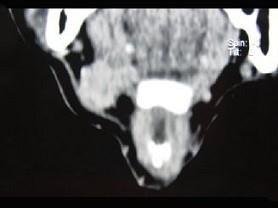

问题 男,45岁,右侧颌下扪及一包块约4个月,无痛,PE:包块质硬,表面欠光整,移动度较差,CT如图所示,最可能诊断是()

选项 A.颌下腺神经源性肿瘤 B.颌下腺腺瘤 C.颌下腺淋巴瘤 D.颌下腺腺癌 E.颌下腺转移瘤

答案 D